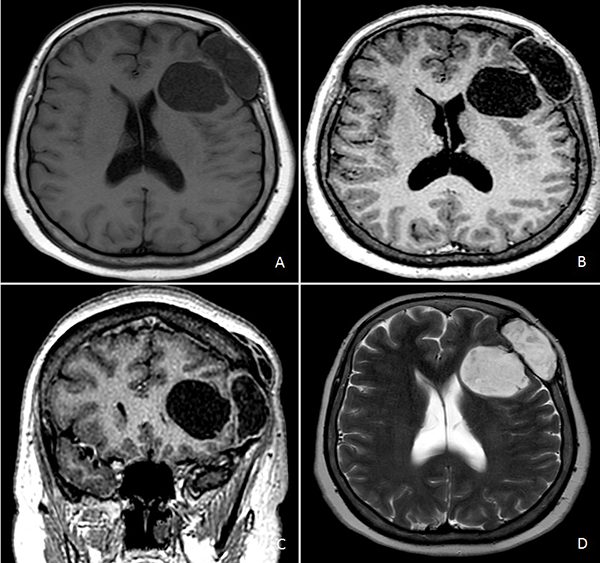

Figura 2. RM de cerebro. A) Secuencia T1 sin contraste endovenoso. B) y C) Secuencia T1 con contraste endovenoso. D) Secuencia T2.

Resonancia magnética (RM) de encéfalo con contraste endovenoso evidenció una lesión heterogénea, predominantemente hipointensa en secuencia T1, hiperintensa en T2, heterogénea e isointensa con respecto al parénquima cerebral en Flair (Fluid attenuated inversión recovery), con escasas áreas de restricción en la secuencia difusión (DWI) y realce fino periférico tras la administración de contraste (Figura 2). Se observó efecto de masa leve con colapso de asta frontal de ventrículo lateral homolateral. Se realizó una angiotomografía de encéfalo para valorar la vascularización adyacente de la masa y descartar anomalías vasculares, siendo negativa para las mismas.